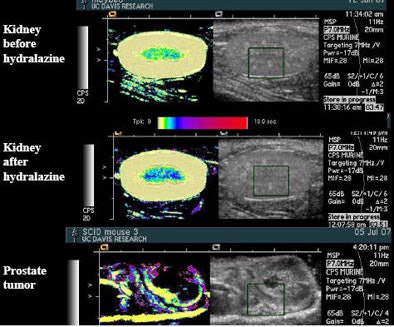

![]() |

| Drugs such as hydralazine and dopamine can be used to perturb the flow of microbubble contrast agents to improve the depiction of perfusion in an organ. The main change seen after administration of the drug hydralazine in the rat kidney, above, was that flow rate slowed, represented by a darker blue in the medulla. Experiments with the flow-perturbing drugs have been shown to be easily reproducible. |

"We can quantify the increase in the amount of time we slow it down by using a drug like dopamine, and if we make multiple measurements of the same region, our standard deviations are small," she said. "These are really good, repeatable studies for this kind of technique." And the ultrasound results can be compared to MRI.